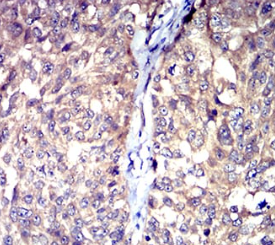

HTR3A Mouse Monoclonal antibody[3B11]

The product of this gene belongs to the ligand-gated ion channel receptor superfamily. This gene encodes subunit A of the type 3 receptor for 5-hydroxytryptamine (serotonin), a biogenic hormone that functions as a neurotransmitter, a hormone, and a mitogen. This receptor causes fast, depolarizing responses in neurons after activation. It appears that the heteromeric combination of A and B subunits is necessary to provide the full functional features of this receptor, since either subunit alone results in receptors with very low conductance and response amplitude. Alternatively spliced transcript variants encoding different isoforms have been identified.

Immunogen:    Purified recombinant fragment of human HTR3A (AA: extra 24-157) expressed in E. Coli.